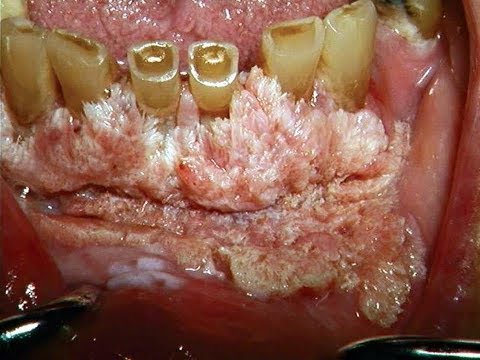

What Snus Can Do To Your Gums | Dipping & Oral Cancer - Snus Siberia - In this video Dr. Joseph Nemeth discusses snus, snuff, dipping and other forms of chewing tobacco or smokeless tobacco. Smokeless tobacco is a type of ...